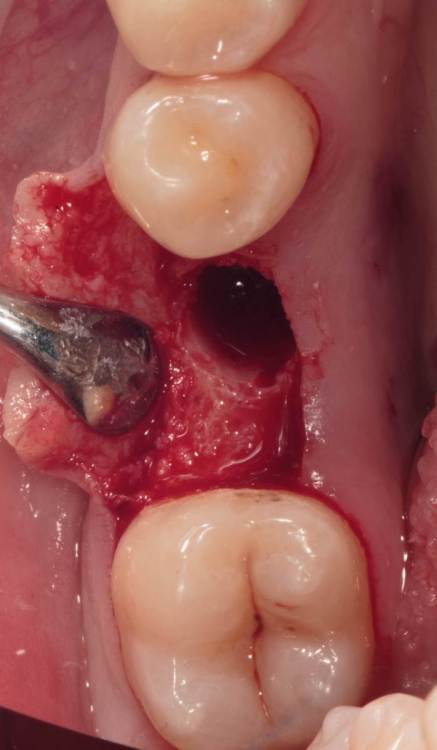

Женька Опубликовано 19 августа, 2023 Поделиться Опубликовано 19 августа, 2023 ?️. Поймал себя на мысли, что испытываю проблемы с ушиванием+ССТ на формике. А именно-не устраивает результат "прирощённой" десны. Вроде на ушивании есть + к объёму, а на протезировании "яма" вестибулярно лишь немного уменьшилась. Подскажите, как лоскут формировать так, чтобы в слоёном пироге имплантат-формик-сст оставался объём слизистой, а не таял. Подумал, что может стоит при имплантации сразу формировать асл. А в кейсе я снова "согрешил" и поставил ультра-низкий формик. В этот раз без всяких послаблений лоскута и натяжения, кмк. Ссылка на комментарий

Борис80 Опубликовано 31 августа, 2023 Поделиться Опубликовано 31 августа, 2023 (изменено) Евгений, а если попробовать и подсыпать и подсадить? Просто объема не хватает, трансплантат меньше требуемого Изменено 31 августа, 2023 пользователем Борис80 Ссылка на комментарий

Женька Опубликовано 19 ноября, 2023 Автор Поделиться Опубликовано 19 ноября, 2023 (изменено) прошло 3 месяца. Изменено 19 ноября, 2023 пользователем Женька порядок фоток 1 Ссылка на комментарий